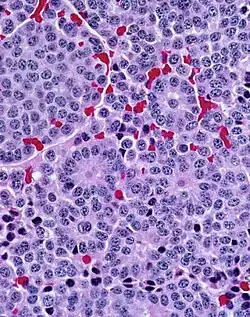

Histopathology of a typical carcinoid tumor of the lung, with prominent rosettes.

Carcinoid tumors are also found in the lungs.